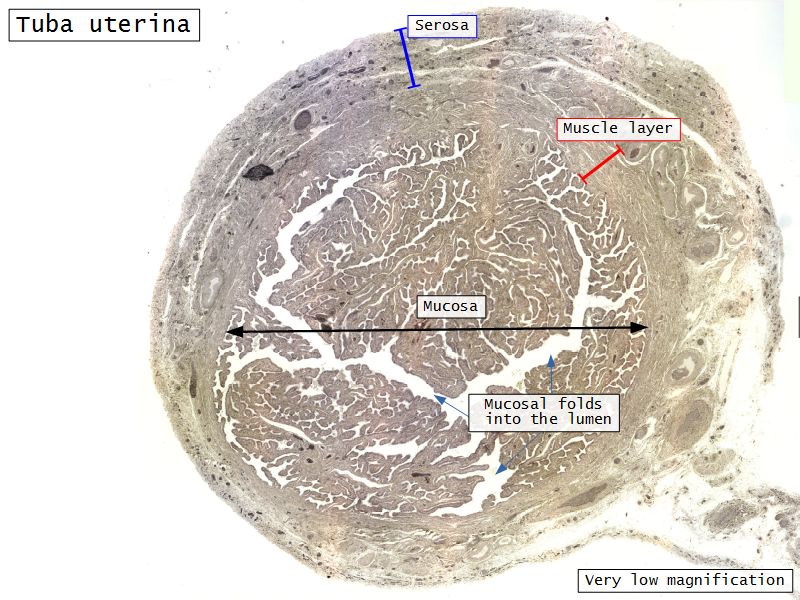

Tuba uterina

Tuba uterina

Three layers

- Mucosa

- Muscular layer

- Serosa

Mucosa

- Epithelium

- Lamina propria

Epithelium

- Simple columnar

- 2 types of cells

- Peg cells

- Secretory cell

- Ciliated cells

- Beats towards uterus

- Facilitate movement of zygote to uterus

Lamina propria

- Loose connective tissue

- Reticular fibres

- Fibroblasts

- Mast cells

- Lymphoid cells

Muscular layer

- Ill-defined

- Inner circular

- Outer longitudinal

- Play role in moving zygote towards uterus

Serosa

- Simple squamous epithelium

- Contains

- Blood vessels

- Lymphatics

- Nerves